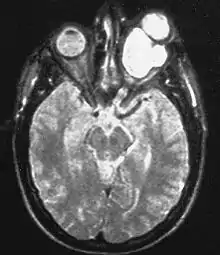

| Magnetic resonance image of a large retrobulbar optic nerve tumor causing massive proptosis | |

Optic nerve gliomas are diagnosed using magnetic resonance imaging (MRI) and CT scans.[5] The tumor adopts a fusiform appearance, appearing wider in the middle and tapered at the ends.[5] Enlargement of the optic nerve along with a downward kink in the mid-orbit is usually observed.[5] While CT scans allow for optic nerve evaluation, MRI allows for intracranial evaluation to observe if the tumor has extended to other regions such as the optic chiasm & hypothalamus.[6]